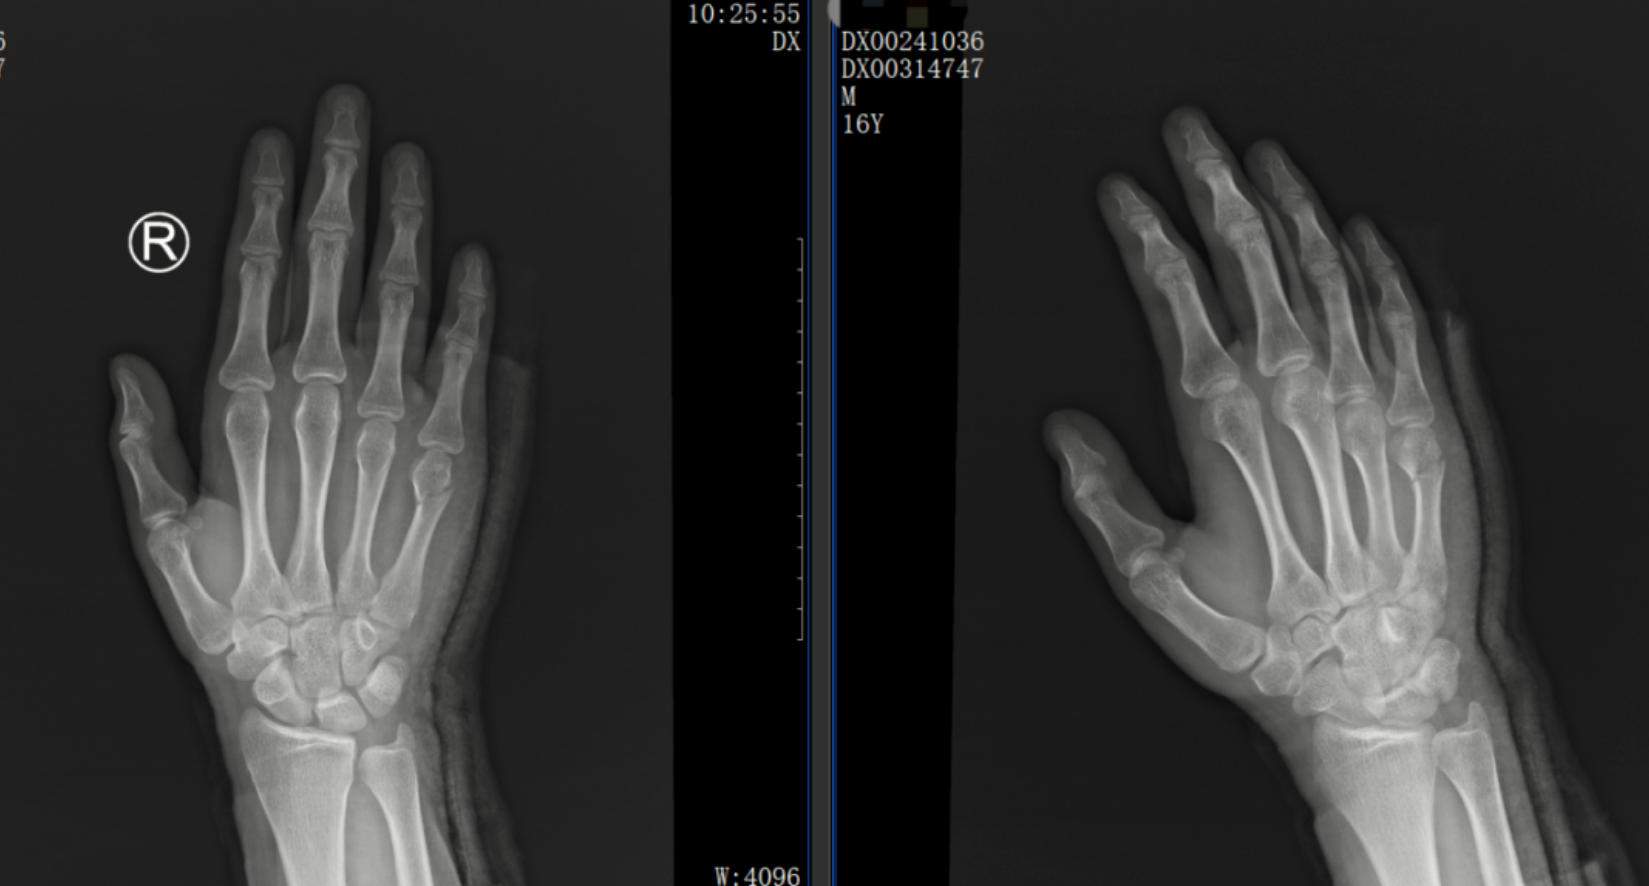

一位16歲的青少年外傷導(dǎo)致右手第五掌骨頸骨折“拳擊手”骨折,為了尋求治療來到我院,經(jīng)過我院中醫(yī)正骨中心醫(yī)師的手法復(fù)位治療,并采用杉樹皮小夾板聯(lián)合石膏固定,3周后,骨痂便順利形成,骨折愈合良好。

正骨前后影像資料